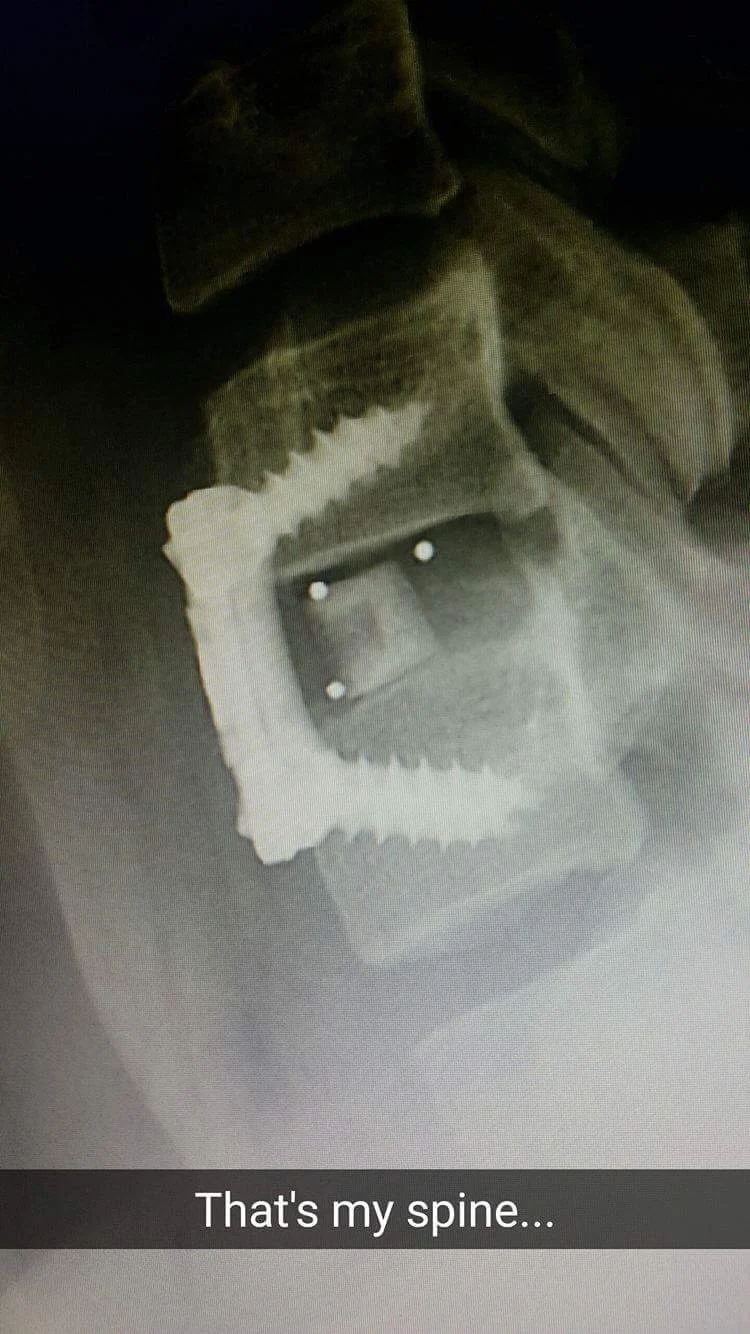

About a week after that I went under the knife at The Alfred Hospital (a week ago at time of writing). They completed a C6/C7 anterior cervical discestomy and fusion. Basically, they removed the problem disc between C6/C7, put in a prosthetic, and then fused both vertebrae with a titanium plate to make sure it doesn't pop out.